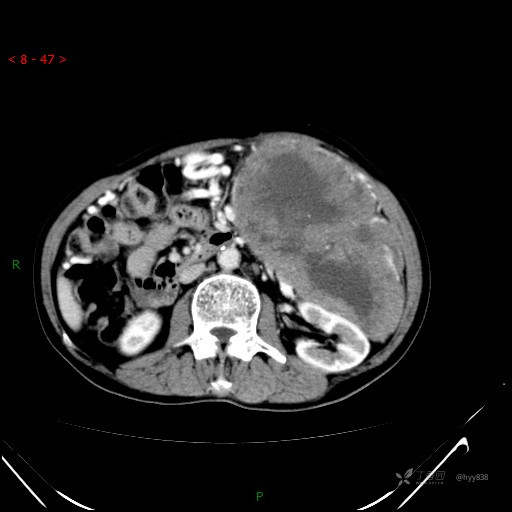

增强静脉期

是病灶太恶、还是患者能忍,腹腔超巨肿物,请会诊---结果公布~

主诉: 左上腹间断疼痛不适近1周

简要病史: 患者1周前出现左上腹间断疼痛,为钝痛,伴左肩部放射痛,无头晕、头痛,无恶心、呕吐、呕血,无便血等不适。为求进一步诊治,门诊以“腹部肿物”收入我科。